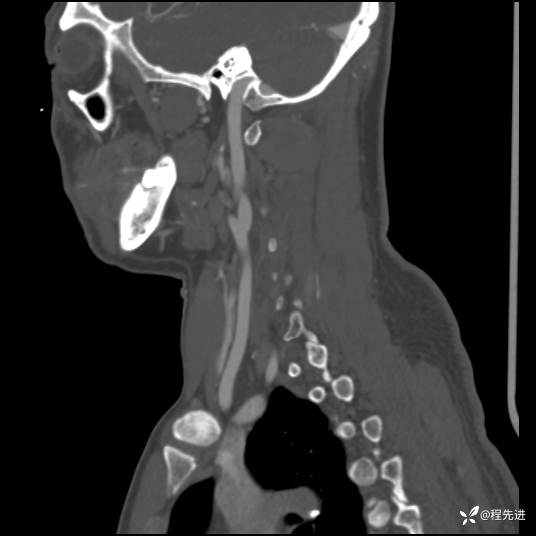

CT平扫+增强: